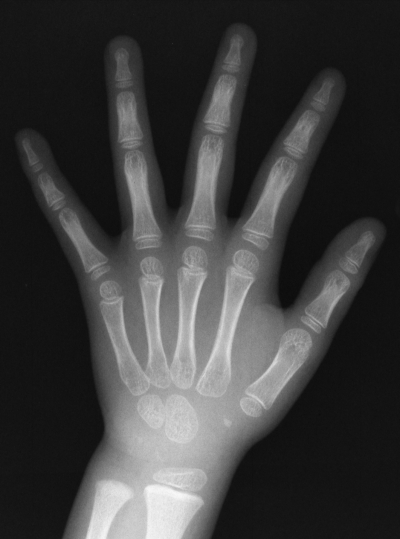

手のエックス線写真を別に示す。考えられる年齢はどれか。1つ選べ。

a. 6か月

b. 1歳

c. 3歳

d. 6歳

e. 9歳